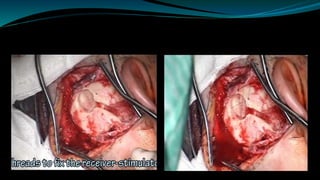

• 32.

• Complete mastoidectomyis performed • Once mastoid antrum is entered LSSC identified and drilling continuous anterosuperiorly until the body of the incus is identified .

Using 1-3 mmdiamond burr facial recess is curefully saucerized with copious irrigation to avoid thermal injury to facial nerve

 A dummyinternal receiver is used to mark out the dimensions of the bony recess

The internal receiveris then placed in the bony recess